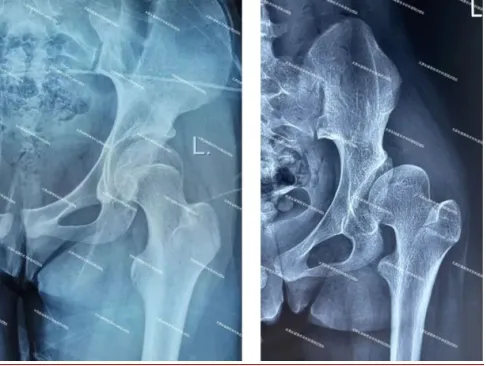

(正常髖關節X線(左圖)顯示髖臼對股骨頭的包容良好;發育不良髖關節X線(右圖)顯示髖臼對股骨頭的包容不足。)